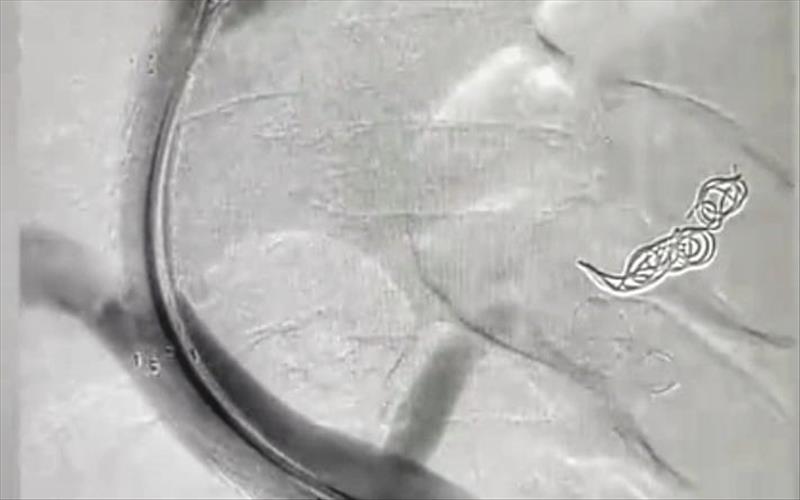

Fatih’te, “nadir romatizmal hastalıklarda güncel tanı ve tedavi yöntemi” konulu seminer düzenlendi.